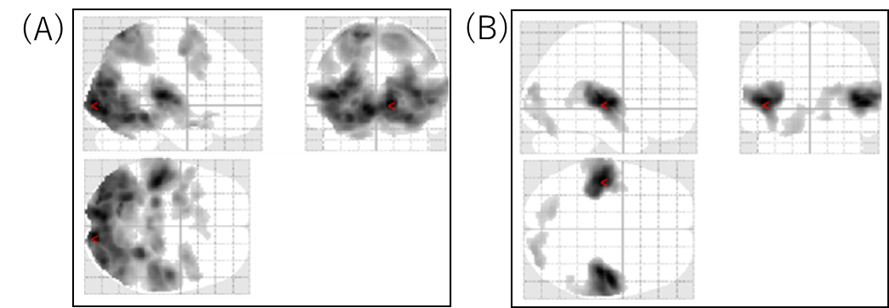

1.(A)動画を見た時の脳の活性化の様子

(B)音を聴いた時の脳の活性化の様子